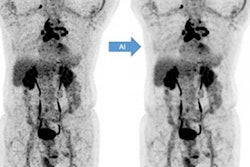

Example 25% low-count PET images, the 25% low-count-enhanced images, and the corresponding standard images for all three scanners for subjects with body mass index (BMI) under 30. (A) A 66-year-old male with BMI of 27 scanned on a Siemens Biograph 64 TruePoint for oropharyngeal cancer (solid arrow pointing to a distant lung metastasis). (B) A 34-year-old female with BMI of 20 scanned on a Siemens Biograph mCT for lymphoma (solid arrow pointing to metastatic lymph nodes and dashed arrow pointing to lesion in the spleen). (C) A 58-year-old male with BMI of 23 scanned on a GE Discovery MI with lung cancer (solid arrow). For all subjects, all low-count images appear considerably noisier compared with the low-count-enhanced and standard images. Note: SUV display scale is 0-7. Image courtesy of npj Digital Medicine."All three readers who analyzed the diagnostic utility of the two sets of PET scans consistently rated the low-count enhanced scans as noninferior to the standard scans," the researchers wrote.